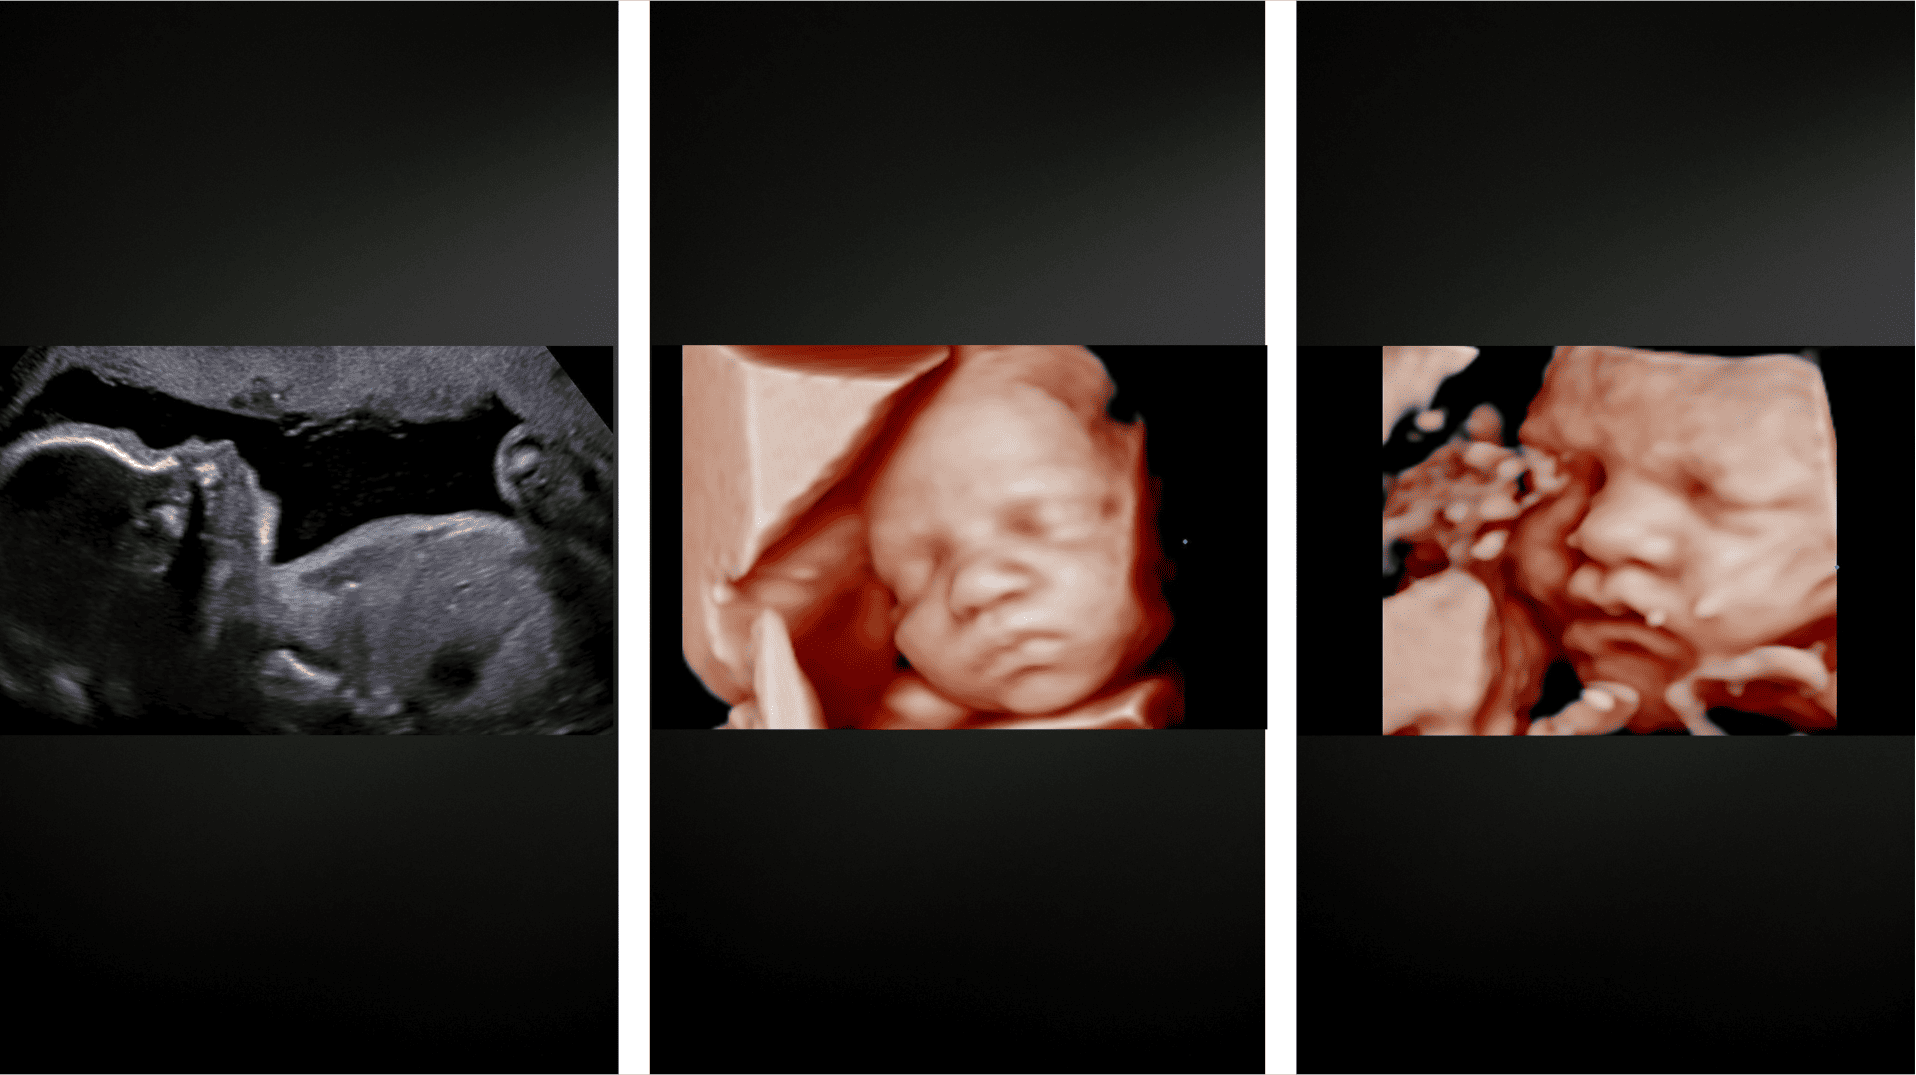

Discover our complete range of ultrasound services for pregnant women, designed with the highest precision and attention to detail to accompany you during this special stage.